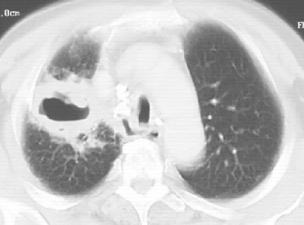

图1-2 男性,44岁,咯血1个月,浸润型肺结核

浸润型肺结核多见于成年人,起病缓慢,临床症状视其病灶范围及人体反应性而定。早期及病灶较小者往往无明显症状及体征,常由健康查体时的胸部X线检查发现,显示为锁骨上下片状、絮状阴影,边缘模糊。当人体处于过敏状态且有大量结核菌进入肺部时,病灶呈干酪样坏死、液化,进而形成空洞及病灶的支气管播散(图1-2)。浸润型肺结核伴大片干酪样坏死灶时,常呈急性进展,出现严重毒性症状,临床上称为干酪性(或结核性)肺炎。干酪样坏死灶部分消散后,周围形成纤维包膜;或空洞的引流支气管阻塞,致使空洞内干酪物难以排出,凝成球形病灶,称为“结核球”(图1-3)。当病变处于炎症渗出、细胞浸润甚至干酪样坏死阶段,经恰当的抗结核化学治疗后,炎症吸收消散;遗留的细小干酪样病灶经纤维包围,逐渐失水、干燥甚至钙化,成为残留的结节状病灶,称纤维硬结病灶或临床痊愈。